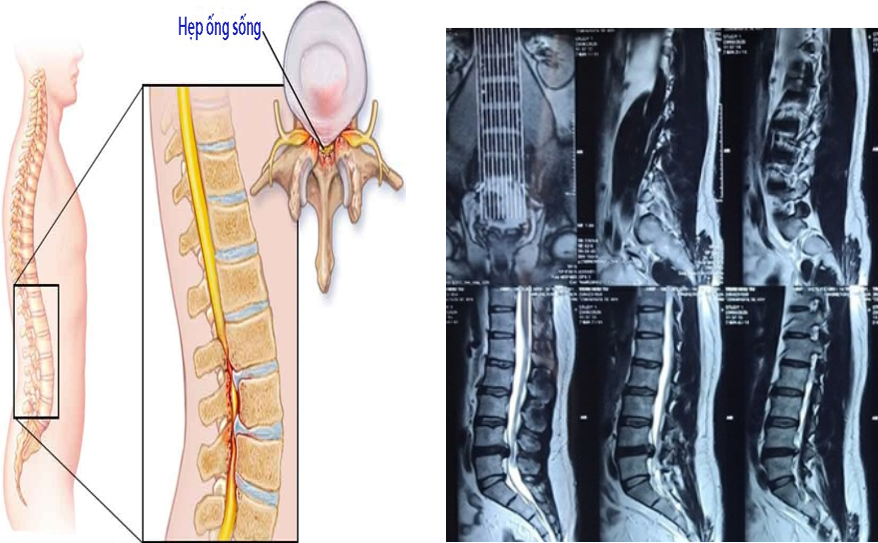

Hẹp ống sống thắt lưng

Hẹp ống sống thắt lưng là sự thu hẹp của ống sống thắt lưng chèn ép các ống tủy sống và rễ thần kinh ở trước khi chúng thoát ra khỏi lỗ liên hợp.

Hẹp ống sống được chẩn đoán dựa trên các triệu chứng lâm sàng kết hợp với cận lâm sàng trong đó xét nghiệm chẩn đoán chủ yếu là MRI cột sống.

- MRI cột sống

2. Hình ảnh: Internet, khoa Chẩn đoán hình ảnh BV Đa khoa Tỉnh Quảng Trị